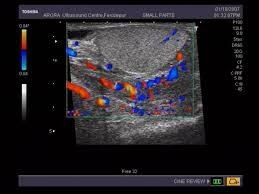

Η διάγνωση γίνεται με την κλινική εξέταση και με εξετάσεις αίματος CRP και ΤΚΕ (αποτελούν δείκτες φλεγμονής) γενική και καλλιέργεια ούρων που συνήθως αναδεικνύουν τον αιτιολογικό παράγοντα και υπερηχογράφημα οσχέου σε συνδυασμό με έγχρωμο Doppler –triplex όρχεων ο οποίος θα αποδείξει τη διόγκωση της επιδιδυμίδας καθώς και την έντονη υπεραιμία και θα παρέχει πληροφορίες για μια άλλη σοβαρή κατάσταση με παρόμοια συμπτώματα που απαιτεί επείγουσα χειρουργική επέμβαση που ονομάζεται συστροφή όρχεος.